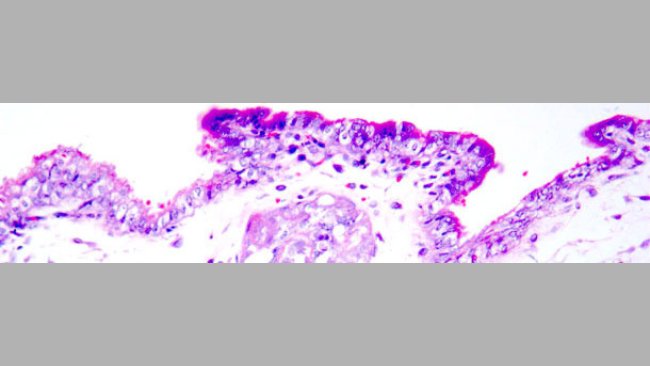

Besamung von Jungsauen mit PCV2-infiziertem Sperma: Auswirkungen auf die Reproduktion und Schutz durch PCV2-Impfstoff für Sauen

Eine PCV2-Impfung der Jungsauen vor der Besamung mit PCV2-infiziertem Sperma führt zu einem deutlich geringeren Virusgehalt sowie einer deutlich geringeren Virusausscheidung und somit zu einem besseren Schutz der Feten.